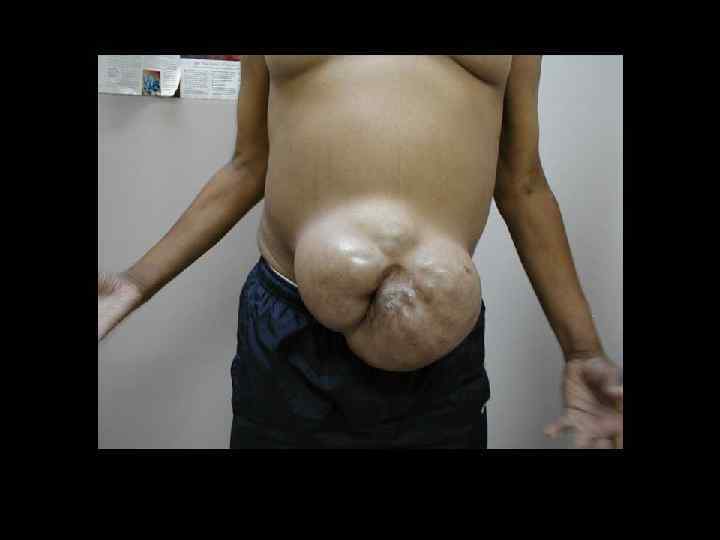

НЕВПРАВИМАЯ ГРЫЖА Возникает при сращении грыжевого содержимого и стенки грыжевого мешка. • невозможно вправить грыжевое содержимое в брюшную полость • невозможно пальпировать грыжевые ворота ЛЕЧЕНИЕ – ПЛАНОВАЯ ОПЕРАЦИЯ

УЩЕМЛЕННАЯ ГРЫЖА Внезапное сдавление содержимого грыжи в грыжевых воротах. • внезапная резкая боль • невправимость ранее вправимой грыжи • резкое напряжение грыжевого выпячивания • отрицательный симптом кашлевого толчка